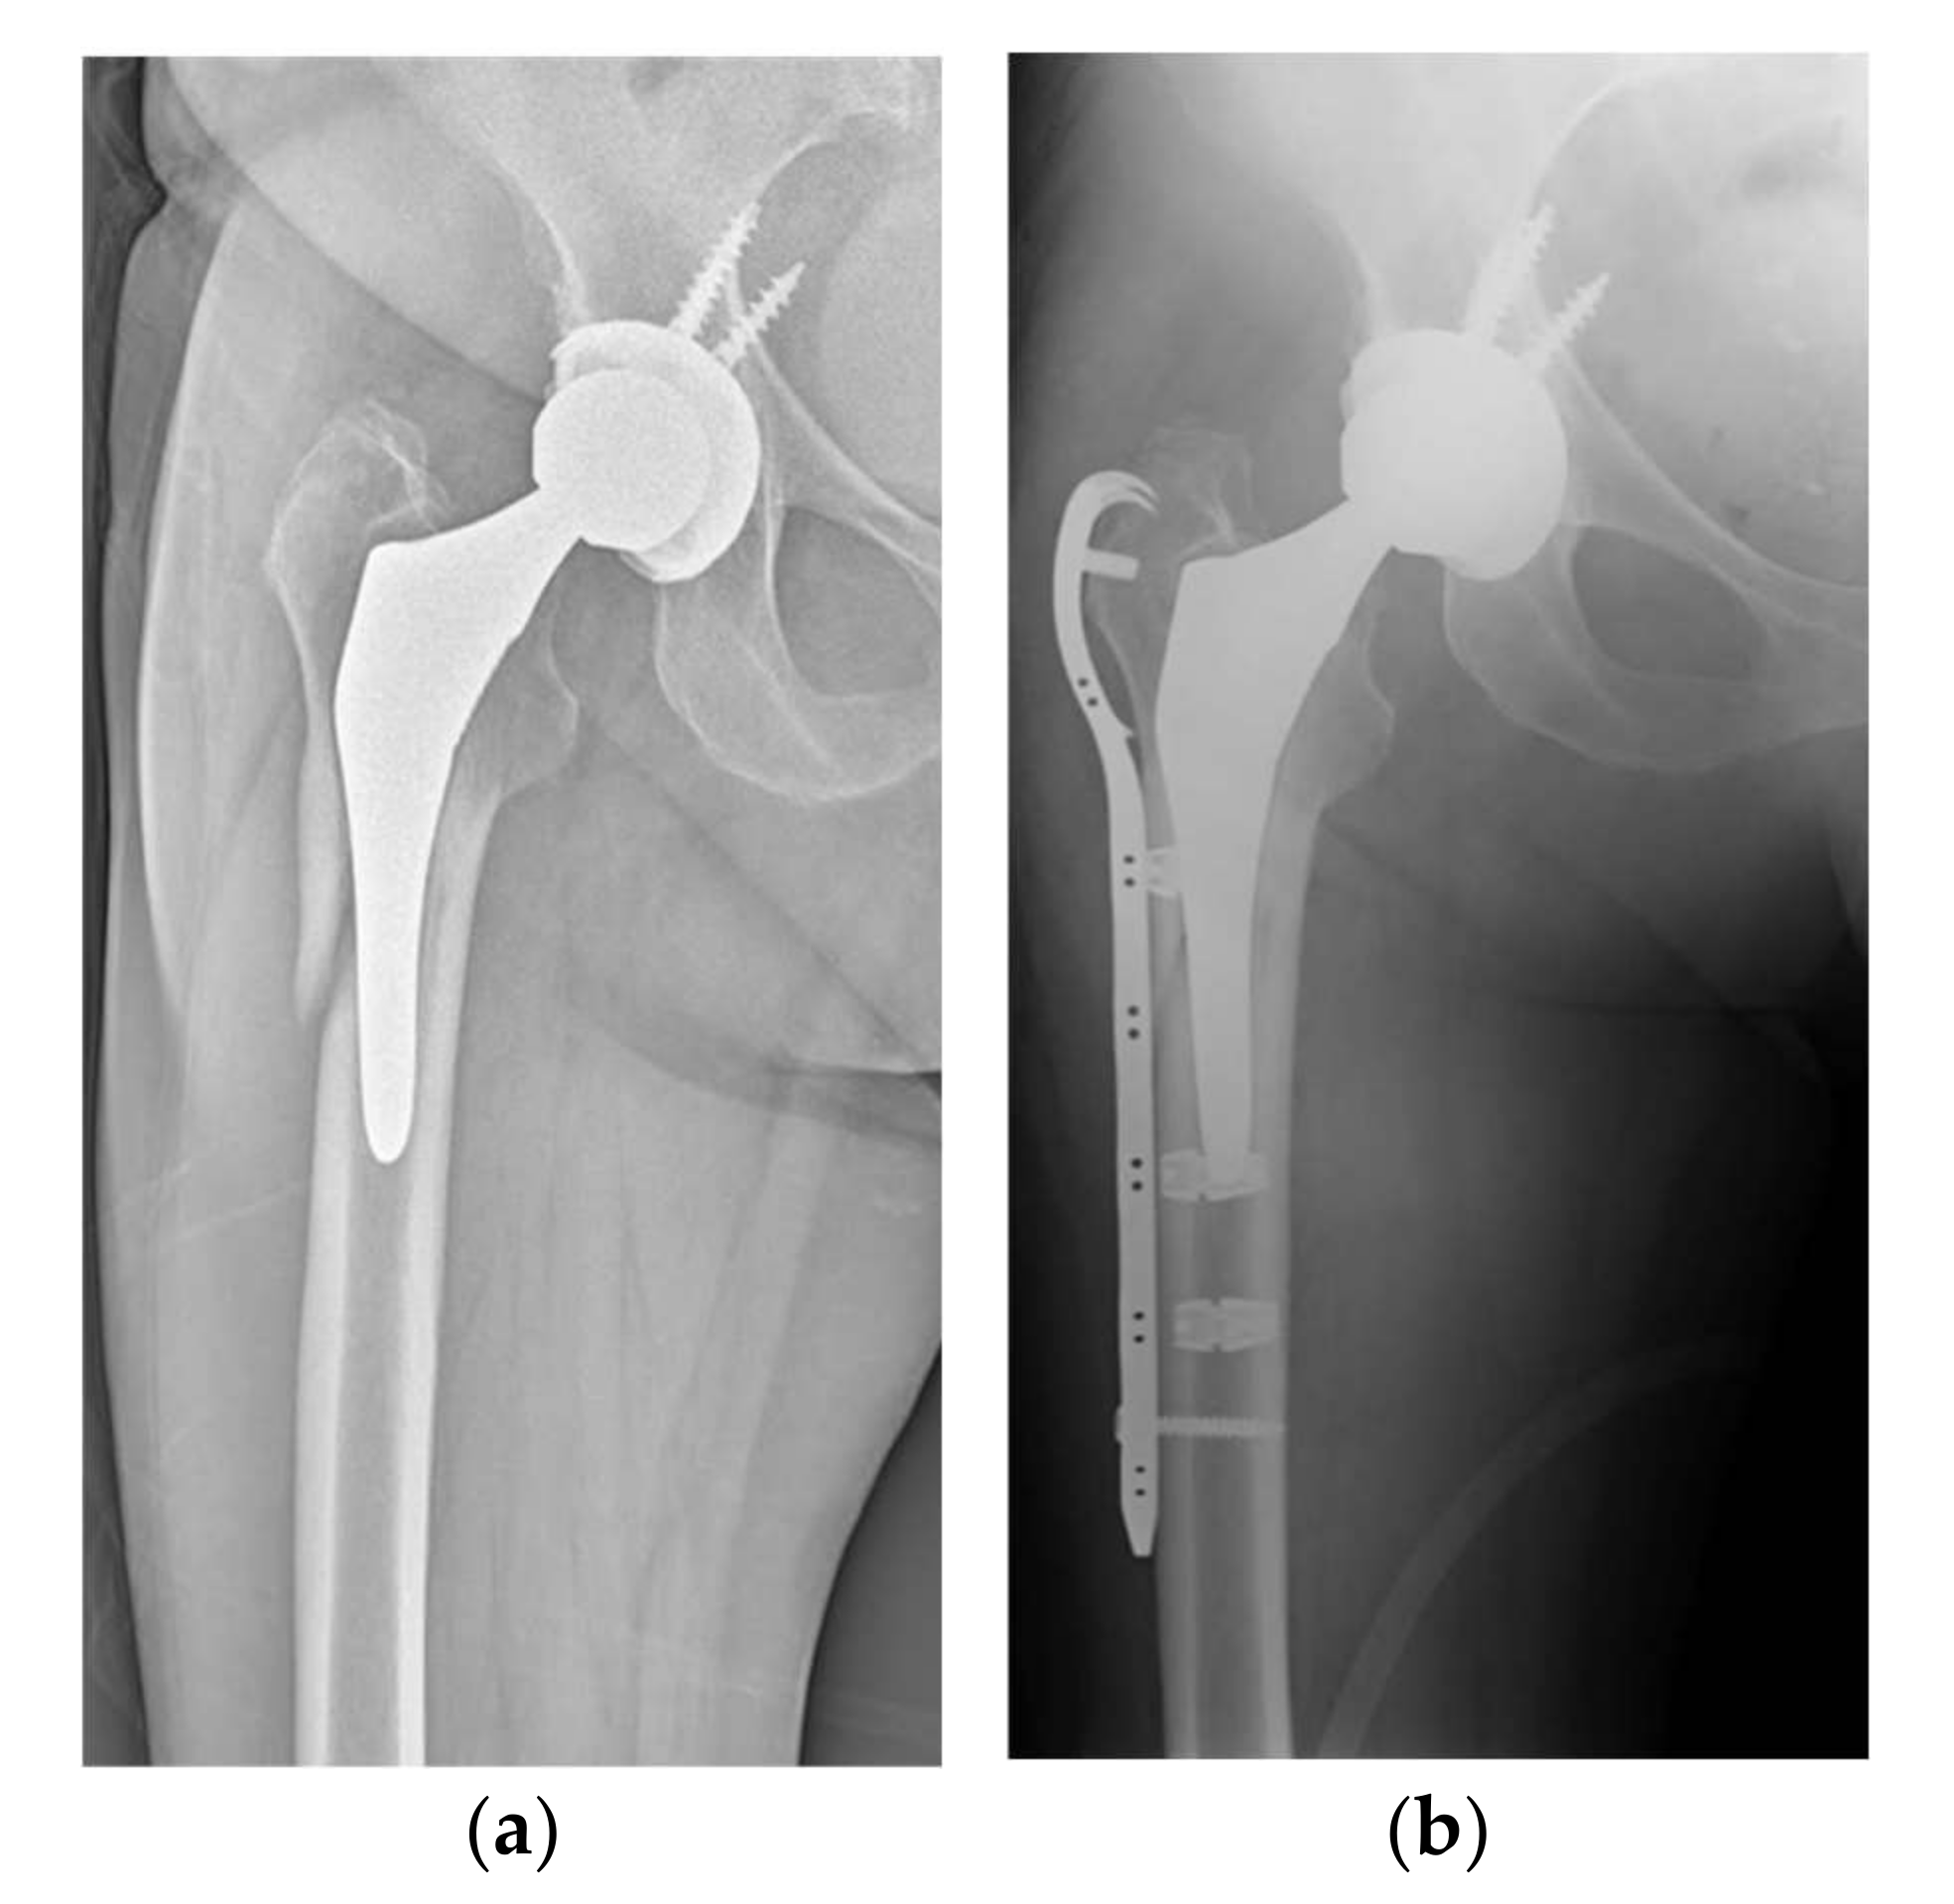

Figure 2.

(a) Preoperative X-ray of type B1 fracture in 76-year-old patient; (b) postoperative 3-month follow-up after placement of a plate with UHMWPe cables.